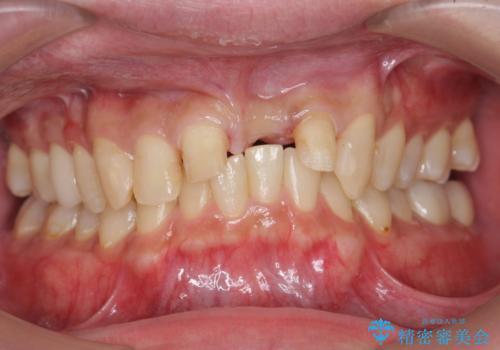

- 以前、前歯にボールが当たりダメになってしまって抜歯したが、そこにとりあえず接着剤で歯をつけて生活していたとのこと。

両側の歯の接着剤の周りが虫歯になってしまっていました。

両側の歯の虫歯をしっかりとってブリッジにすることにしました。

欠損部に長年薄いプラスチックの仮の歯を留めていたため、下の歯が食い込みさらにブリッジのポンティックの隙間がない状態でした。そのため、かみ合わせが深く、下の歯との隙間がかなりなかった為、事前の矯正治療をお勧めしましたが、希望されず特に行わずそのまま虫歯治療を行うことになりました。

かみ合わせが深く、歯ぎしりでブリッジに負担がかかるため、ナイトガードを作成し、就寝時使用していただいています。